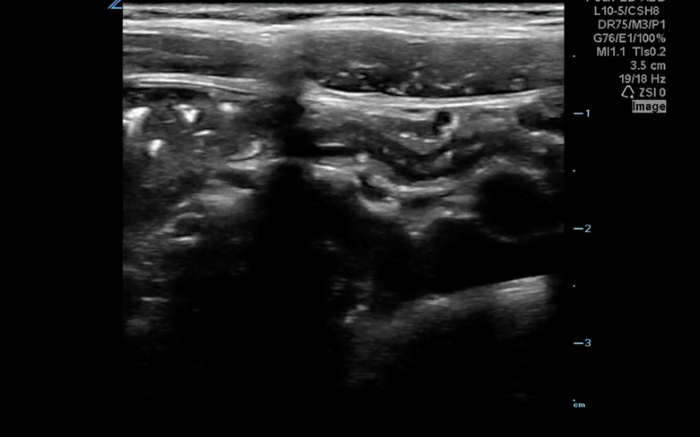

The linear probe is placed in the RLQ in the transverse position with indicator to the patient’s right. Identify the psoas muscle and iliac vessels lying medial. Once these structures are visualized, slide lateral and look superficially to identify the cecum. (Figures 1a,1b 1) Use graded compression-progressive increase and decrease of pressure to move any gas out of view. Keeping the lateral edge of the abdominal cavity in view (Figure 2), the ultrasound probe should slide cranial in traverse plane, visualizing the ascending colon until the hepatic flexure.  In this location, the colon turns just medial to the liver with the kidney deep in the view. (Figure 3) This is the most common location to identify ileocolic intussusception. If no tissue mass is identified, the probe should be turned to the sagittal plane with indicator toward the head (to keep the colon visualized in the transverse view) and moved across the transverse colon continuing to use graded compression to look for a tissue mass consistent with intussusception. Once at the splenic flexure (Figure 4), the probe should be transitioned back to the transverse orientation to interrogate the descending colon.

10-2024 Article7-1a.pngFigure 1a. Unlabeled anatomy of identifying landmarks of RLQ to identify cecum.